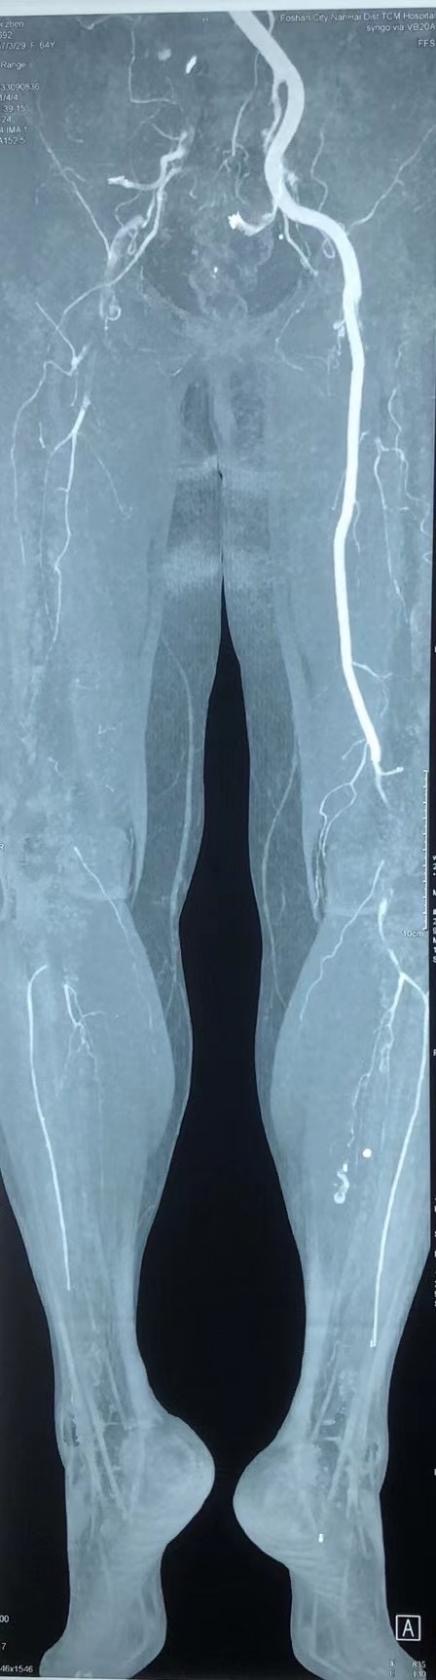

一天晚上,64岁的邬女士(化名)在家突发右下肢麻木,进而快速发展成右下肢剧烈疼痛,整段大腿变得冷冰冰的。她强忍疼痛来到广医二院急诊,医生查体后发现她右下肢皮温凉,股动脉、腘动脉、足背动脉搏动消失,血管造影发现她整个右下肢血管几乎不显影,右髂动脉、股动脉、腘动脉管腔充满了血栓。

手术中,广医二院张智辉教授带领血管外科团队协同作战,经邬女士右侧腹股沟切开一个3厘米的口子,暴露股总动脉、股浅动脉和股深动脉,然后又切开股总动脉。医生在探查中发现其股总动脉没有血流,血栓充满整个管腔。于是,医生们在X光引导下往其股总动脉切口近端送入导丝和取栓导管至髂动脉,取出红色长段血栓约40厘米,然后又往远端送入导丝和导管至腘动脉,取出长血栓约60厘米。

手术中,医生团队反复取栓直至邬女士股动脉远近端都喷血良好,再无血栓取出后,又血管造影再次确认她下肢血栓被取干净,且无向远端膝下和足背的动脉和对侧髂动脉脱落。术后,邬女士右下肢皮温变暖,足背动脉搏动强,血供恢复了。